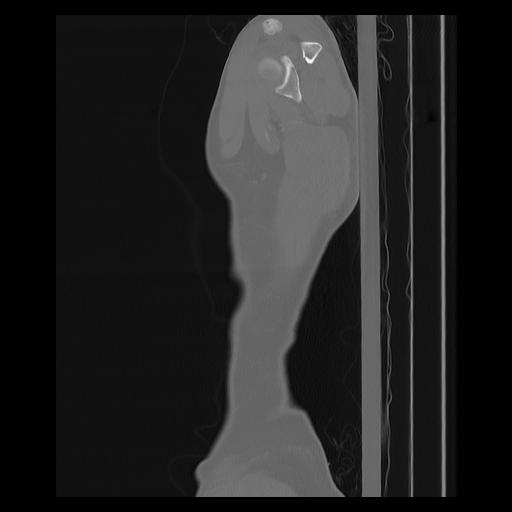

33 PULMON,CE,Sagittal,3.000,PULMON,Sagittal,